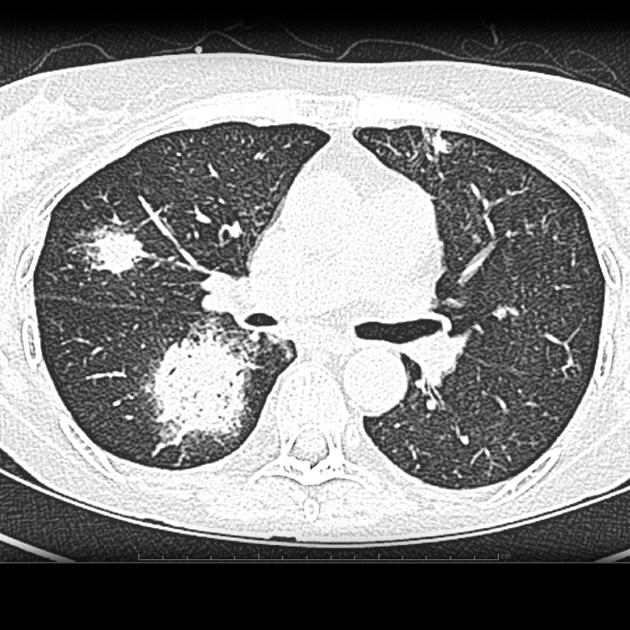

КТ при грибковой пневмонии выявляет следующие анатомические признаки:

В нативном режиме определяется наличие инфильтративных очагов с нечёткими или лобулярными контурами, преимущественно в нижних или средних долях, что указывает на активное грибковое поражение лёгочной ткани.

В режиме сканирования мягких тканей визуализируются зоны консолидации с элементами воздушных включений, формирующих феномен "полумесяца" или "ауры", что отражает наличие некроза и воспаления.

В режиме высокоразрешающего сканирования лёгочной ткани выявляются слабовыраженные узелки с окружающей зоной "матового стекла", а также формирующиеся полости распада с тонкой или утолщённой стенкой.

В режиме реконструкции в нескольких плоскостях уточняется анатомическая распространённость очагов, вовлечение плевры, наличие плеврального выпота и контакт с бронхиальным деревом.